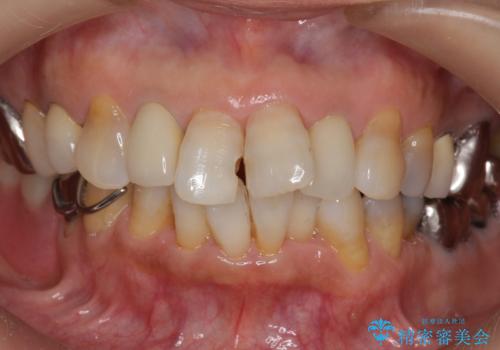

- 前歯の詰め物が頻繁に外れるとのことで来院。

これを機にセラミックでかぶせて、前歯の歯並びも良くしたいとのことでした。

左上の前歯のみねじれが大きいため、歯の位置をひっこめたかぶせものにするために、神経の治療を行っています。

両側の前歯もやり替えをすることで、前歯の前突感も無くしています。